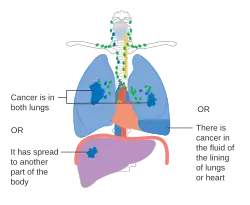

De stadiëring van niet-kleincellige longkanker (NSCLC) vindt in eerste instantie plaats aan de hand van de TNM-classificatie 8ste editie. Deze is gebaseerd op de grootte van de primaire tumor, verspreiding naar lymfeknopen (nodes) en metastasen (uitzaaiingen). Vervolgens wordt op basis van de TNM-parameters de kanker in een groep ingedeeld, die kan variëren van "occulte kanker" (kanker waar de primaire tumor nog niet gevonden is) tot de stadia 0, IA, IB, IIA, IIB, IIIA, IIIB en IV. Deze indeling in een stadiumgroep helpt bij de keuze van behandeling en het inschatten van de prognose.[43] Kleincellig longkanker (SCLC) wordt vanouds geclassificeerd als 'beperkt stadium' (beperkt tot één helft van de borst en binnen het bereik van één enkel verdraagbaar radiotherapieveld) of 'uitgebreide stadium' (verspreide ziekte).[2] De TNM-classificatie en -groepsindeling zijn echter nuttig bij het inschatten van de prognose.[43]

- Schema van belangrijkste kenmerken van longkanker stadiëring

Stadium IV longkanker